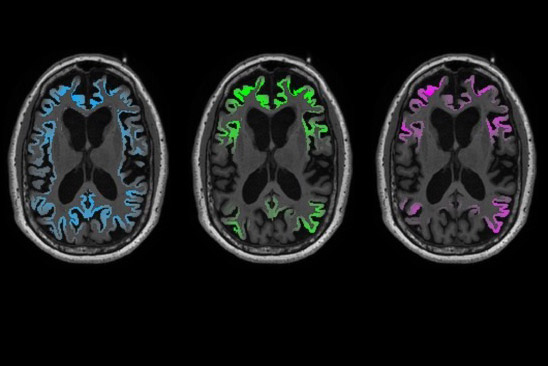

Tau PET brain scans (green) in early clinical-stage Alzheimer’s patients accurately predict the location of brain atrophy measured by MRI 1–2 years later (magenta). Amyloid PET imaging (blue) does not predict the location of either tau or future brain atrophy.

The researchers found that overall tau levels in participants’ brains at the start of the study predicted how much degeneration would occur by the time of their follow up visit (on average 15 months later). Moreover, local patterns of tau buildup predicted subsequent atrophy in the same locations with more than 40 percent accuracy. In contrast, baseline amyloid-PET scans correctly predicted only 3 percent of future brain degeneration.